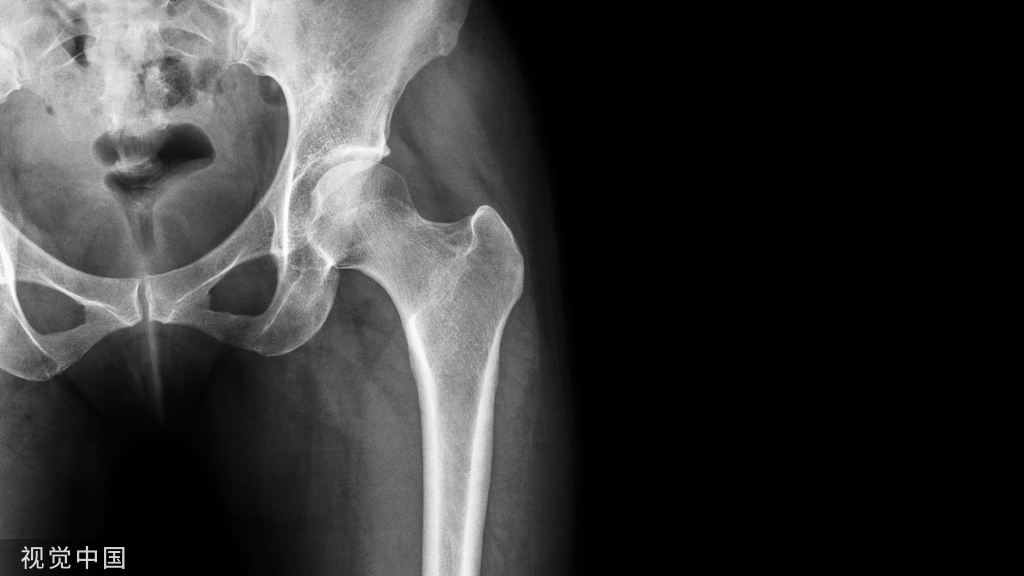

3种情形,建议取

1.儿童体内的内固定物。儿童由于年龄太小,骨骼系统正在发育,放在体内的内固定物因为有可能会影响到骨的发育和形态,所以建议取出。

2.内固定物触及到了皮肤,导致疼痛。有些部位皮包骨头,比如肘关节、锁骨、踝关节、膝关节前方等,这里的骨折,放上内固定物之后,皮肤下面就是内固定物,很容易在日后发生问题。比如膝盖前方髌骨的内固定可能会影响到跪地的动作,而肘关节后方的钢板可能会在弯曲胳膊肘时顶到皮肤。所以这些皮包骨头部位的内固定物如果已经产生了疼痛的症状,就要取出。就算现在还没有症状,但是预计在患者的预期生命里或者结合患者的自身工作性质可能以后会造成影响的,也应该取出。

3.出现感染、皮肤溃烂、内固定物外露。这种情况说明此处的软组织已经出现问题,很可能已经感染或者即将出现感染,如果X片显示骨折已经愈合,最好立即取出内固定物,以便很好的控制感染。